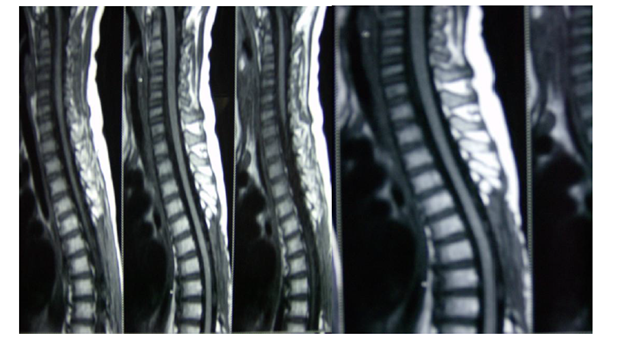

A previously healthy 5year old male child presented with complaints of weakness of both lower limbs. He had fall a week before the presentation of the weakness. His bladder and bowel habits were normal. On Examination Lansky Score 90 - minor restrictions in strenuous physical activity.1 His higher functions were normal, in his motor functions tone was normal, power was 4/5 –right Lower Limb; 3/5- Left lower limb. His deep tendon reflex, plantar and sensory systems were normal. He had scoliosis. On investigations Blood and Urine examinations were normal. Radiograph of the Chest and Ultra sonogram of abdomen were normal. Radiograph of the Dorsal Spine showed scoliosis. Magnetic Resonance Imaging of Brain was normal. Magnetic Resonance Imaging Spine showed Extra Dural mass lesion in the right dorso-lateral aspect of Spinal Cord at D 6-D 8 Vertebral Level causing significant cord compression (Figure 1). He underwent Dorsal Laminectomy with removal of Extradural SOL on 26-04-06. Per-op: Moderately vascular, Greyish fleshy mass, spreading in the extradural space extending from D-6 to D-8 level compressing the spinal cord. Near total excision was done. Pathological findings showed Small round cells with perivascular infiltration and pseudorosettes, suggestive of Malignant Primitive Neuro Ectodermal Tumour of Extra dural Origin (Figure 2). Immmuno Histo Chemistry Studies Done showed CD99 +ve , Vimentin +ve, MIC2 +ve. Post operatively Boy was treated with one cycle of chemo [VAC] Vincristine, Adriamycin, Cyclophospamide. Since there was minimal residue and Malignant histology ,a course of post-op external radiotherapy was planned using Linac using multi leaf collimator, 3D CRT Plan ,the post op tumor bed (with adequate margin ) was treated with Photons-6 MV Dosage: 42Gy in 28 # 150cGy /# over 6weeks using 3 portals. At the end of radiotherapy (Figure 3). Patient was able to walk with Spinal support. Post op and Post RT Post RT 3 more cycles of VAC and 4 cycles of Vincristine, Actinomycin-D, Cyclophospamide alternating with 8 cycles of Ifosfamide and Etoposide were given starting from May 2006 to March 2007 and the patient withstood the treatment without major morbidities. PET scan of the whole body done in Jan 2007 showed Radioisotope: 18F-FDG-370MBq/45min uptake. PET-3D mode and CT Extent of study: Base of skull to upper mid third of thigh, showed no evidence of any active disease anywhere in the body (Figure 4). Patient is now in complete remission and on follow up for 10years (Figure 5).

Figure 1 MRI Spine showing the mass lesion in Extradural space in the Dorsal spine at D 6-D 8 Level.